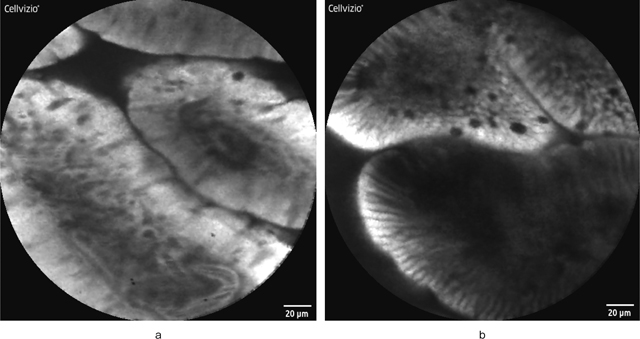

筆者はpCLE導入後から現在までに170例以上の症例においてfluorescein dripping methodで検査を行っているが,fluorescein静脈投与では必発である尿の黄染も含めて副作用の出現を経験していない 9).また,fluorescein dripping methodの妥当性のため,fluorescein静脈投与後および滴下後の消化管粘膜内におけるfluoresceinの分布を解析したところ,短時間でほぼ同等の粘膜・細胞内分布を示すことを確認している 10).一方,fluorescein dripping methodのデメリットは静脈投与と比較して血管の描出が弱いという点であるが(Figure 4),粘膜表層から55-65μm程度の深度に存在する微小血管の評価はNBI併用拡大観察で容易に行えることを考えると,あえてリスクを冒して静脈投与にこだわる必要はないのではないかと筆者は考える.勿論,内視鏡検査時のfluoresceinの静脈投与のみならず粘膜滴下も保険収載されていない現状では,日常検査時のfluorescein使用自体が困難であることにはかわりない.Fluorescein使用によるpCLEの実施に関しては,今後,多施設での症例の蓄積と安全性の確認が必要である.

Fluorescein投与法と共焦点内視鏡画像.

a:fluorescein静脈投与後の十二指腸正常絨毛の共焦点内視鏡所見.間質内の微小血管内を蛍光色素剤が流れることによって,血管の輪郭が白色明調に描出され,血管内を流れる暗調の赤血球がリアルタイムに観察される.

b:fluorescein粘膜滴下後の十二指腸正常絨毛の共焦点内視鏡所見.絨毛構造自体の画像はaとほぼ同等であるが,aと比較して血管の描出が悪い.